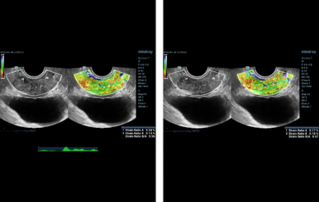

??? ?? ??? ?? ???? ? ??? ?? ??? ?? ??? ??? ??? ???. ???? ??? UWN+ ?? ?? ??? ?? MI??? ??? ??? ?? ?? ??? ?? ?? ?? ???, ?? ?? ?? ???? ??? ? ????.